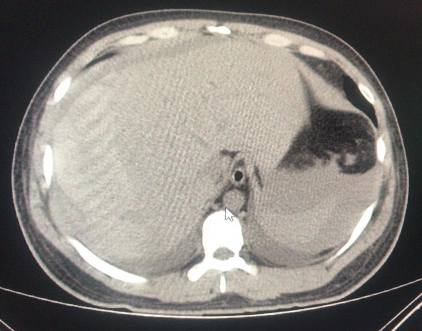

ERCP was performed successfully over 0.035-inch diameter guidewire, a Haraldsson type 3 duodenal papilla;3 Cholangiography showed a fill defect of 8mm, with a no bleeding, complete sphincterotomy, the common bile duct stone was extracted with balloon, without complication. Patient was followed for 6hours, and previous discharge, pain appeared at right upper quadrant. Colicky pain, diaphoresis, nausea and vomiting. We made new laboratory test, showing, and a drop of hemoglobine from 15g/dl previously to 10g/dl creating us the idea about patient was bleeding, maybe from the sphincterotomy, just giving no surgical management until then. Urgent computed tomography (CT) scan exhibited 13x11 cm subcapsular hepatic hematoma on the surface of the right hepatic lobe (Figures 1-4). He was treated with conservatory management with Tomographic control every 10days in 2 episodes, and every 2months, with hematoma regression until the month 6th.

Figure 1 Dilated bile duct, intraductal stone.